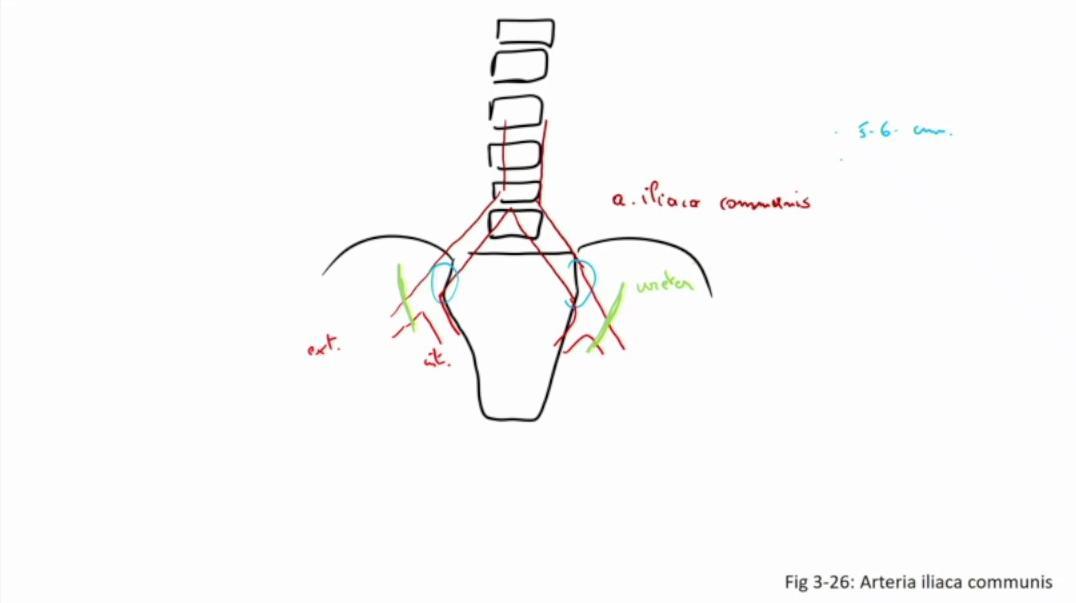

Fig 3.26: a. iliaca communis

|

|